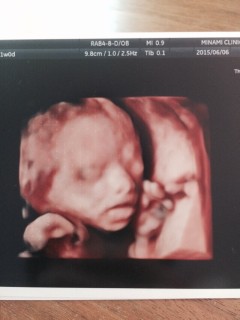

初4Dエコーで女の子だと判明しました。体重は346gでした。 もう少し見ていたかったなー。早く会いたい。

初の4dで見てもらいましたー!

すっごい顔がリアル!恥ずかしがりやなのか手で顔をずっと隠してました(笑)